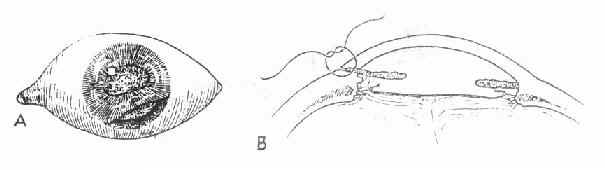

治疗:①瞳孔缘或基质裂口无特殊处理。严重的虹膜根部离断伴有复视症状时,可考虑行虹膜根部缝合术,将离断的虹膜缝合于角巩膜缘(图15-3)。②外伤性瞳孔散大时,轻者可能恢复或部分恢复,重者不能恢复。伴有调节麻痹时,可配眼镜矫正近视力。

图15-3 外伤性虹膜根部离断缝合方法